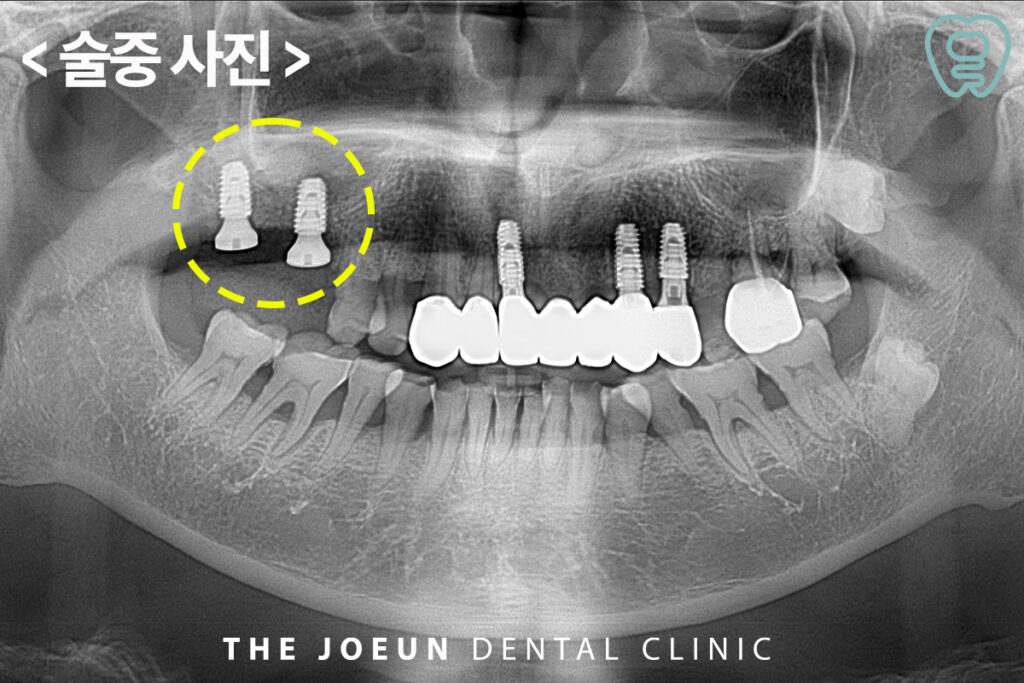

약 3개월 후 상악동 거상술과 임플란트 식립을 동시에 진행하였는데요.

상악동 거상술은 측방 접근법과 치조정 접근법으로 나뉘어 뼈 부족이 심한 경우는 잇몸을 절개한 후 측면에 작은 창을 내고 막을 들어 올려 뼈 이식재를 넣는 측방 접근법을 시행하고 뼈가 일부 부족한 경우에는 임플란트 삽입 위치를 통해 상악동을 직접 들어 올리고 이식재를 채우는 치조정 접근법을 사용합니다. 환자분께서는 측방 접근법을 통해 많은 양의 뼈를 이식한 후 임플란트 식립을 진행하였습니다.